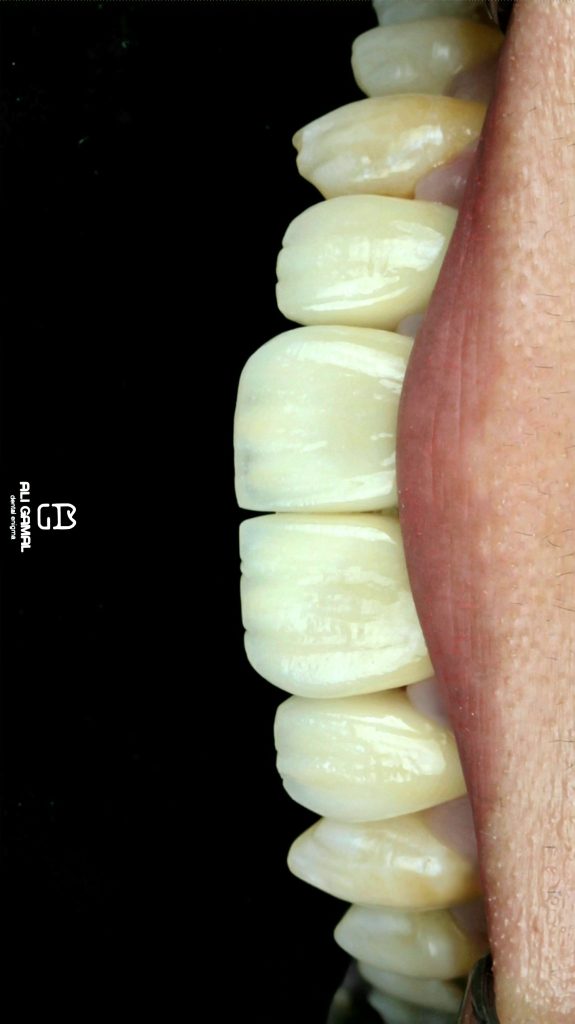

Prosthetic approach should accomodate for soft and hard tissue, respectively to restore smile, contour and function.

Horizontal preparation done for teeth no. 12,11 and 21.

Butt joint veneer preparation done for tooth no. 22.

Custom made post and core done for tooth 12. Followed by connective tissue grafting for discolored root (esthetic purpose).